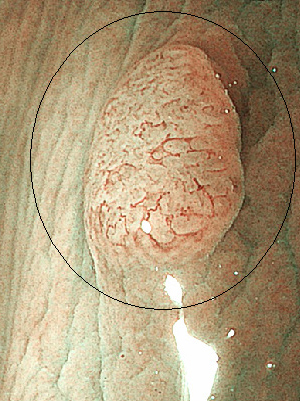

内視鏡検査の所見例

胃体部 胃癌

内視鏡検査の所見例

胃体部 胃癌